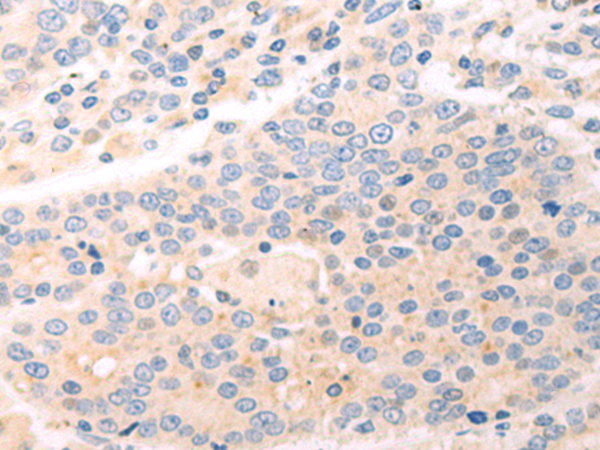

分类: 科研抗体货号: P09449别名: HEI10; C14orf18应用: WB,IHC反应种属: Human, Mouse